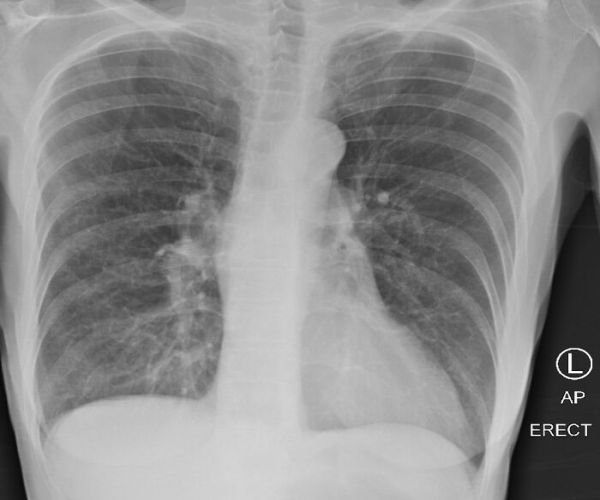

pusac

Белите дробови на пушач покажуваат замагленост.